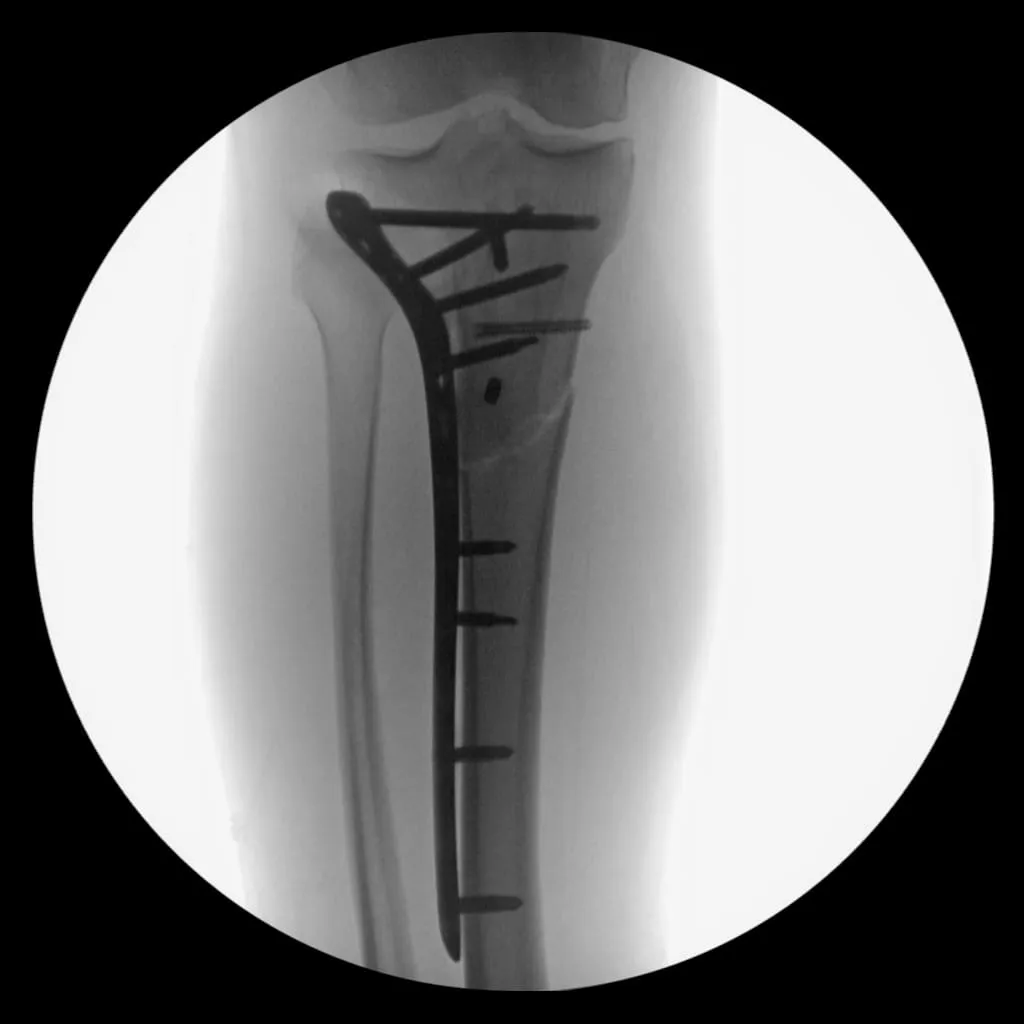

Nine days later, I underwent surgery to install additional hardware to support the fracture. Here is the x-ray from my first post-op appointment.

X-ray showing the titanium rod and screws in my right leg

This marked the third time in eight years that I found myself on crutches and unable to put weight through my leg for 2.5 months. I had to undergo physical therapy three times a week to regain the ability to walk. Four months after surgery, at the end of April, I took my first running steps on a treadmill at physical therapy.